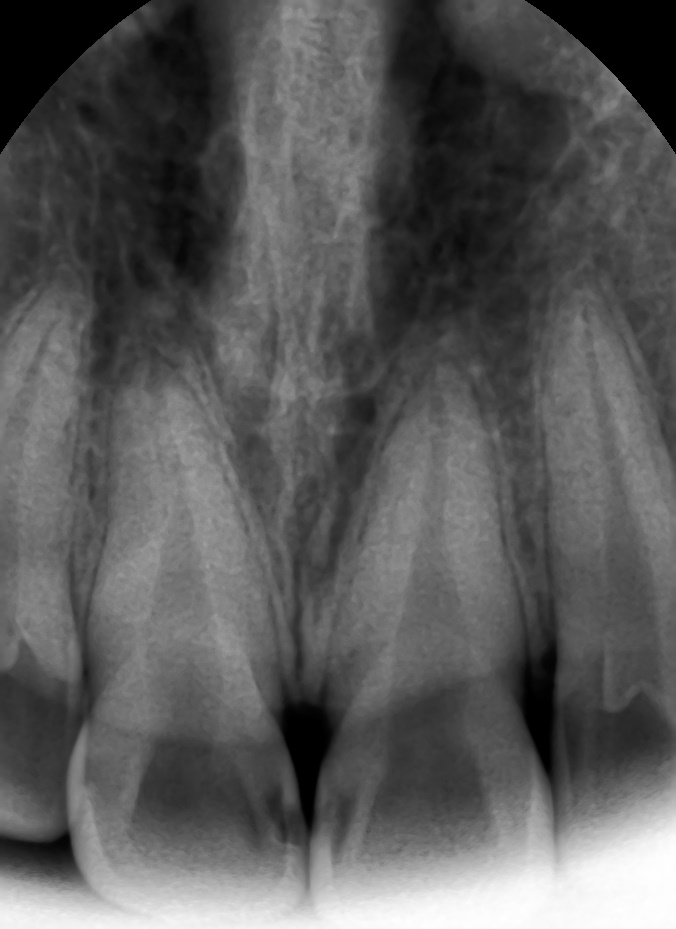

왼쪽 화살표 충치는 엑스레이로 다시 한번 명확하게 확인 하였습니다.

환자분들은 치아를 보여드려도, 엑스레이를 봐도,

잘 구분이 안간다고 하실 수도 있지만

경험이 많은 치과의사의 눈과 엑스레이로 더블체크한 곳은

위의 사진처럼 그 부분을 파보면 분명 충치가 있습니다!